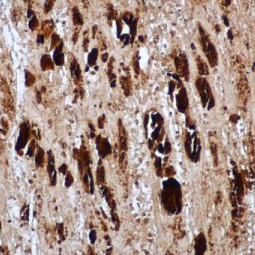

| GeneTex为EV71研究提供出色的抗体,请查看下面热门的EV71研究产品。 |